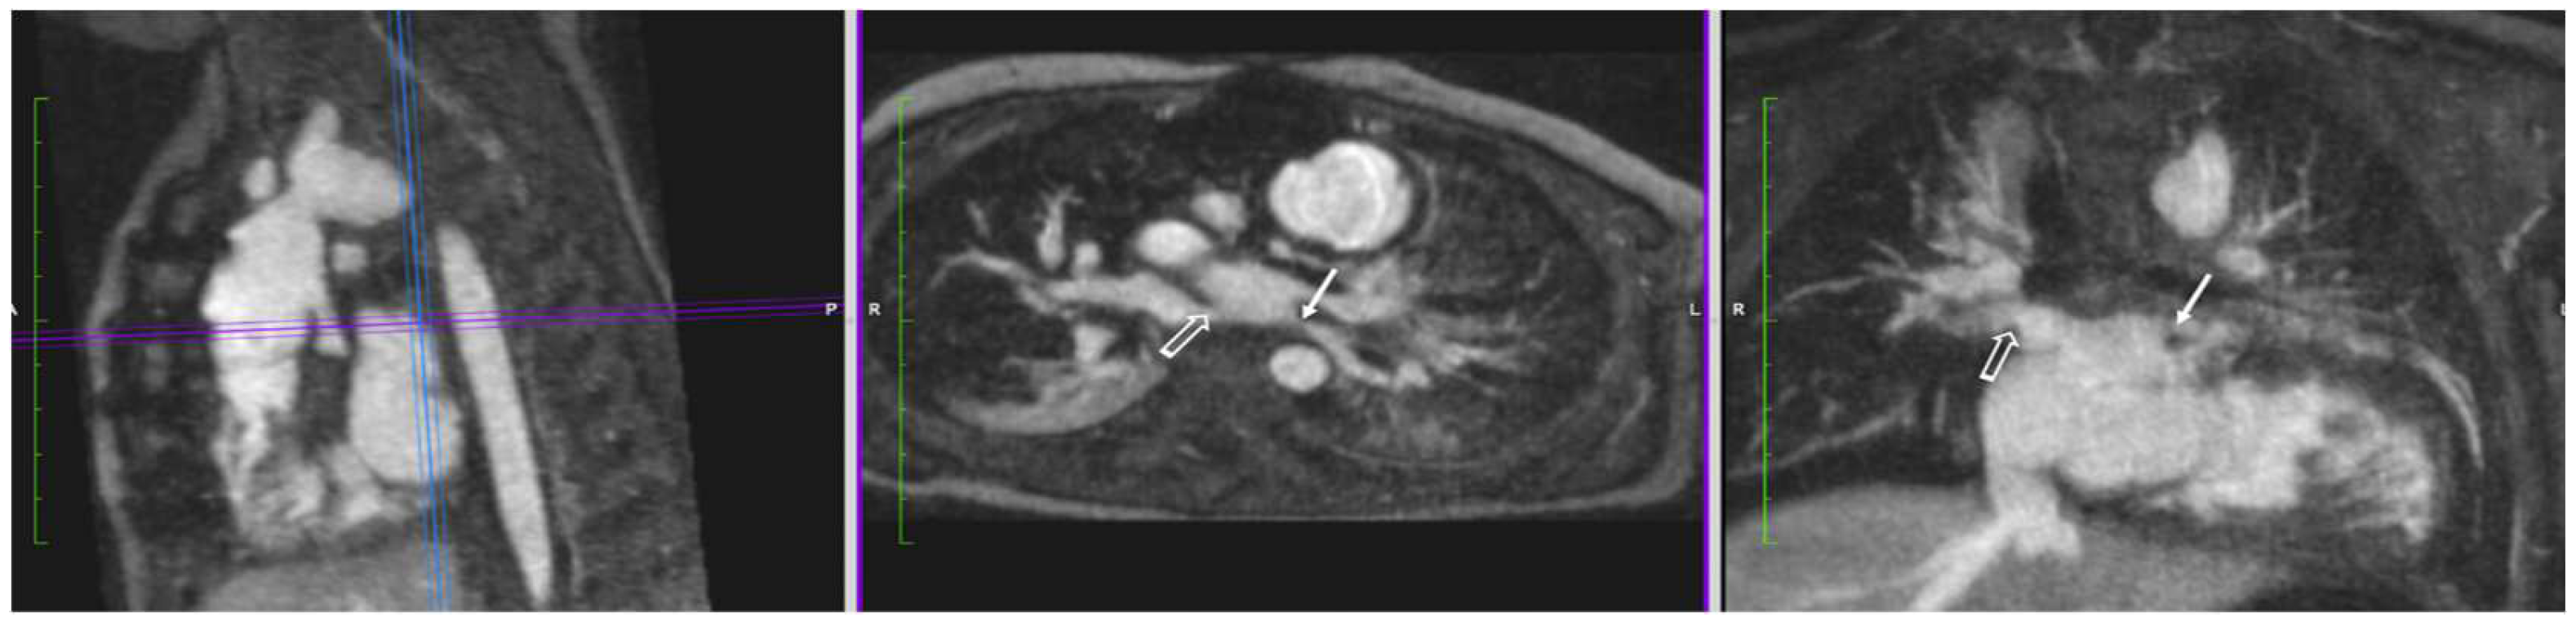

4.3.1. Coarctation of the Aorta

- Shepherd, B.; Abbas, A.; McParland, P.; Fitzsimmons, S.; Shambrook, J.; Peebles, C.; Brown, I.; Harden, S. MRI in adult patients with aortic coarctation: Diagnosis and follow-up. Clin. Radiol. 2015, 70, 433–445. [Google Scholar] [CrossRef]

| Aortic Aneurysm | Genetic syndromes linked to aortic aneurysms and dissection include (among others): Marfan’s, Loeys–Dietz, vascular Ehlers–Danlos, and Turner’s. Bicuspid aortic valve also confers a higher risk. High-resolution imaging of the entire aorta and its branches can be readily achieved with FE steady-state imaging. |